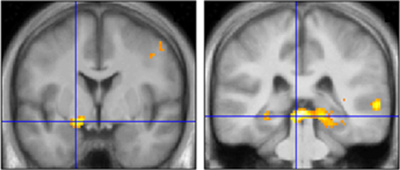

その結果、閾上条件でも閾下条件でも、それた視線に対して、下頭頂小葉・中前頭回といった大脳新皮質の脳部位が強く活動することが分かりました。これらは、注意の移動に関わることが知られている脳部位です。また、閾下呈示の場合に特に、それた視線に対して、上丘・扁桃体といった皮質下の脳部位が活動することも示されました。これらの領域は、無意識での視覚情報処理を担当していると考えられています。こうした結果から、無意識の視線による注意シフトを実現するために、意識的な場合と共通する注意の脳内ネットワーク、さらに意識的な場合とは異なる脳内の別の情報処理経路が関与していることが示唆されます。

閾下条件で特に、それた視線に対する強い活動。無意識で視覚情報を処理する経路と提案されている扁桃体(左)と上丘(右)が活動した。